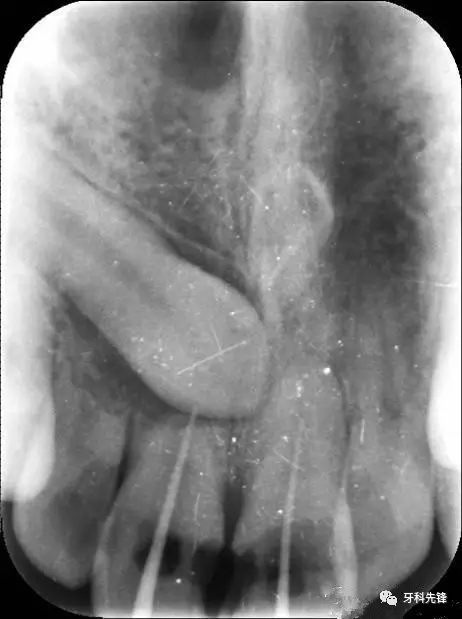

圖1.術(shù)前的根尖片影像:12、11根尖2/3壓迫吸收、11、21根管內(nèi)各有一牙膠尖。